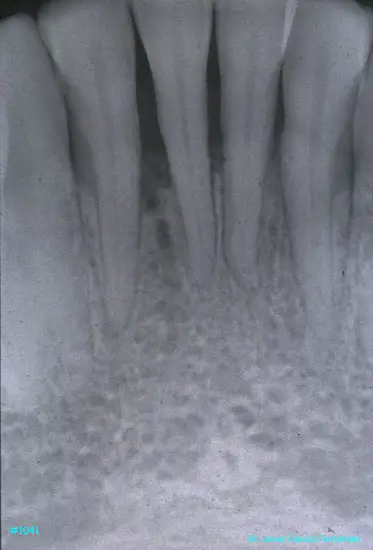

Atlas of Surgical Techniques in Periodontics. Chapter III. Atlas de Técnicas Quirúrgicas en Periodoncia